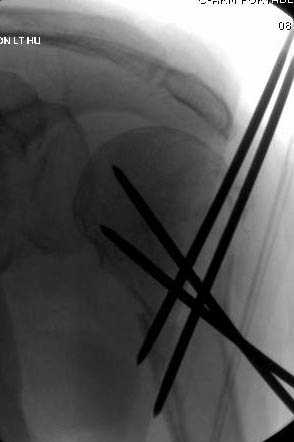

Наличие рентген контроля (ЭОП) помогает во время

репозиции и фиксации, но многие коллеги умудряются без рентгена фиксировать несколькими спицами перкутанно.

Наш недавний случай перкутанной фиксации "методом

Сиэтла" спицами 2.8 мм с резьбой на конце.

Головка плечав небольшом варусе или это проекционное?